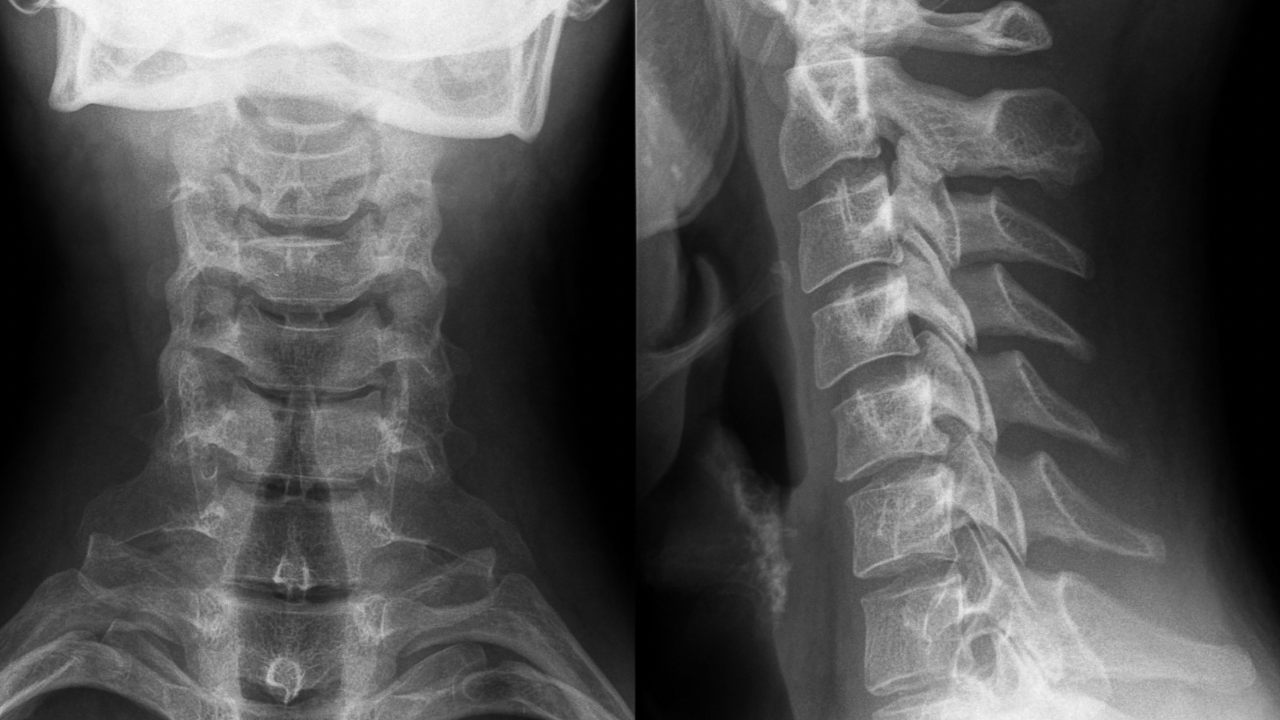

1.ストレートネックとは?現代人に急増する“首の歪み”

ストレートネックとは、

本来ゆるやかに**前弯している首のカーブ(頸椎のカーブ)**が失われ、まっすぐに近い状態

になっていることを指します。

首の骨(頸椎)は7つあり、

通常は「S字カーブ」の一部として頭を支えるバランス構造になっています。